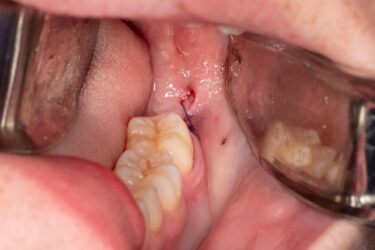

I have a case share. I have a patient who presented with Pericoronitis tooth number #1 and other impacted wisdom teeth. Medical history significant for von Willebrand‘s disease. I had a difficult time getting a medical status update from her PCP. Upon questioning the patient, it looks like a bleeding issues haven’t been too severe for her. However, I was concerned because my treatment plan included the removal of all four impacted wisdom teeth.

In this case, I modified my prescribing regiment to include 650 mg of transexamic acid in addition to analgesic medication. (Sig: instructed to take three times a day for up to four days.)

I had the patient take her first dose of transexamic acid with her oral sedatives one hour pre-op.

I was pleasantly surprised to observe the bleeding control we achieved immediately postop surgery referenced in the photos.